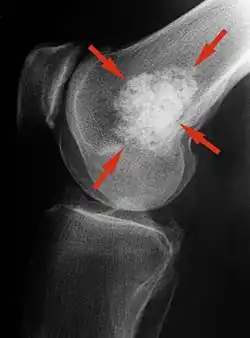

Röntgenbild eines Enchondroms im Ober­schenkel­knochen

kalzifizierendes Enchondrom am distalen Femur

Im Röntgenbild stellt sich das klassische Enchondrom als zur Knochenachse längliche, ovaläre Läsion zentral im Markraum langer Röhrenknochen dar. Eine exzentrische Lage schließt ein Enchondrom jedoch nicht aus. Das Zentrum der Läsion liegt meist in der Metaphyse oder in der distalen Diaphyse eines Röhrenknochens. Ein kleiner oder kurzer Knochen kann vollständig ausgefüllt sein. Typisch für Enchondrome ist eine Ausdünnung der Kortikalis des Knochens von innen, das sogenannte Scalloping und im Falle einer Expansion über das Volumen des Knochens hinaus die Neubildung der Kortikalis (Neocortex). Eine Periostreaktion wird jedoch praktisch nie beobachtet. Das Erscheinungsbild eines Enchondroms wird des Weiteren hauptsächlich vom stark variierenden Ausmaß der Verkalkungen der primär knorpeligen Tumormatrix geprägt: diese können punktförmig, ring- und bogenförmig („rings and arcs“) und flockig sein. Oftmals imponiert das Bild Popcorn-artig. Die Verkalkungen treten häufiger und ausgeprägter in den langen Röhrenknochen auf, während die Läsionen in den kleineren Knochen der Finger und Füße weniger verkalken. Das Röntgen-Bild erfasst sicher nur die Verkalkungen und das Scalloping, so dass das wahre Ausmaß eines nur gering verkalkten Enchondroms mit dieser Methode unterschätzt werden kann. Verschwinden von vormals verkalkten Arealen innerhalb eines Enchondroms im Verlauf muss als Hinweis auf eine Entartung gedeutet werden.[2]